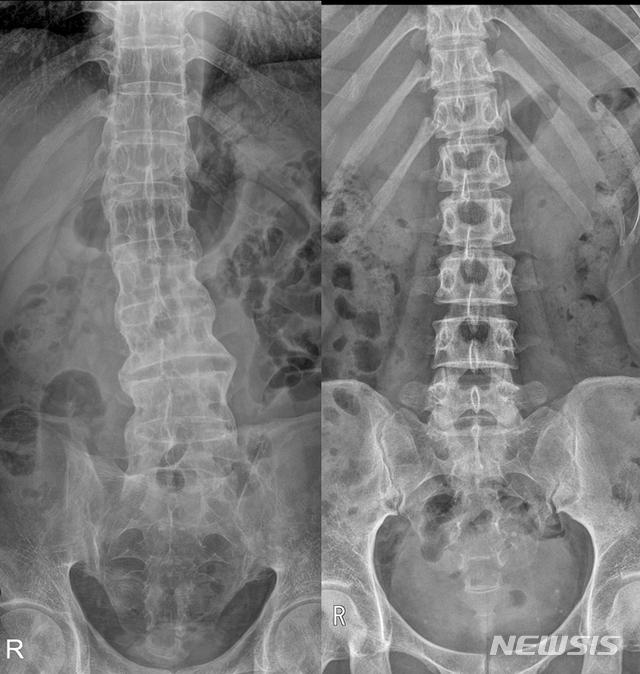

17일 의료계에 따르면 강직성 척추염은 척추와 천장관절 등 관절 부위에 만성적인 염증이 생겨 통증과 뻣뻣함을 유발하는 자가면역질환이다.

강직성에서 '강직'은 '뻣뻣해짐' 또는 '굳는 것'을 의미하고, 척추염은 말 그대로 '척추에 염증이 생기는 것'을 의미한다. 척추 외에 엉덩이, 무릎, 어깨 등의 관절에도 염증을 일으킬 수 있다.

주로 젊은 층에서 발생하며, 조기에 적절한 치료가 이루어지지 않으면 척추뼈가 서로 붙어 움직임이 제한되고 일상생활에 큰 불편을 줄 수 있다. 하지만 조기 진단과 적절한 치료, 생활습관 관리, 규칙적인 운동을 통해 질환의 진행을 늦추고 삶의 질을 유지할 수 있다.